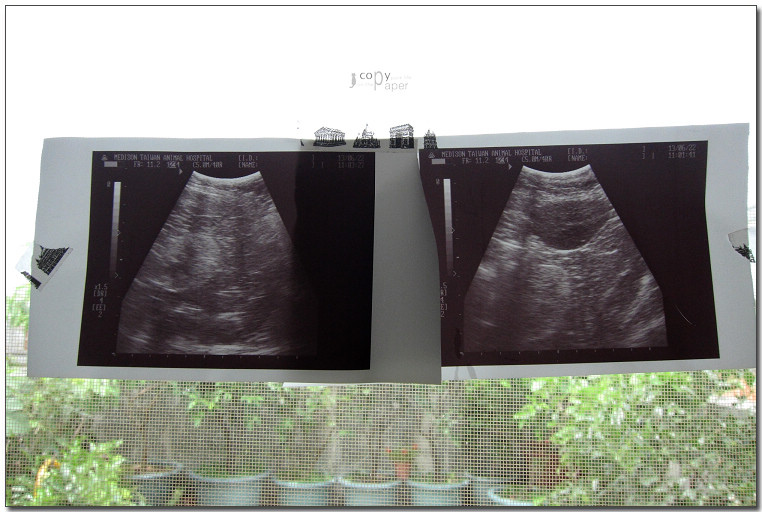

照了X光,

做了超音波,

體重6.4公斤(明明瘦瘦的,怎麼那麼重?),

好像沒什麼大礙,

打了2針,

又拿了二星期的藥,

買了化毛膏。